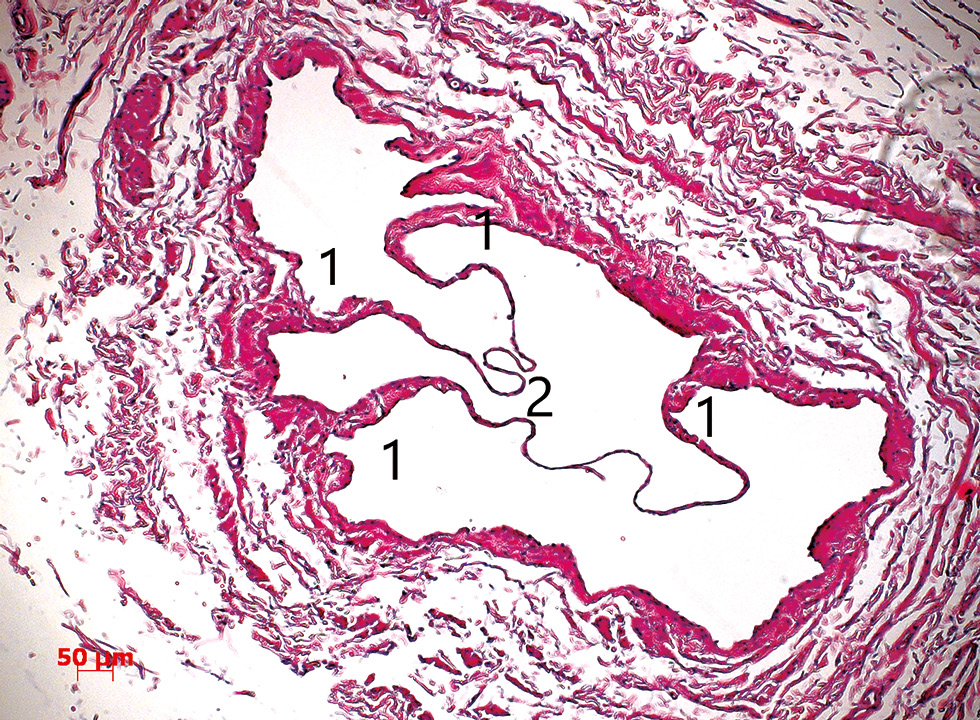

Клапанные паруса или створки представлены двумя подвижными частями, которые и обеспечивают закрытие просвета вены при ретроградном кровотоке. Створки клапана состоят преимущественно из коллагеновых волокон и являются очень тонкими (рис. 3). Это позволяет клапанам, будучи негромоздкими структурами, обеспечивать отток крови в одном направлении. Сторона клапана, обращённая к току крови, покрыта эндотелием, имеющим уплощённую форму. На поверхности, обращённой к синусу, эндотелий более высокий, полигональной формы.

Рис. 3. Клапан глубокой дорсальной вены на поперечном срезе. Определяются клапанные валики (1) и створки (2). Окраска гематоксилин-эозином. Ув. ×100.